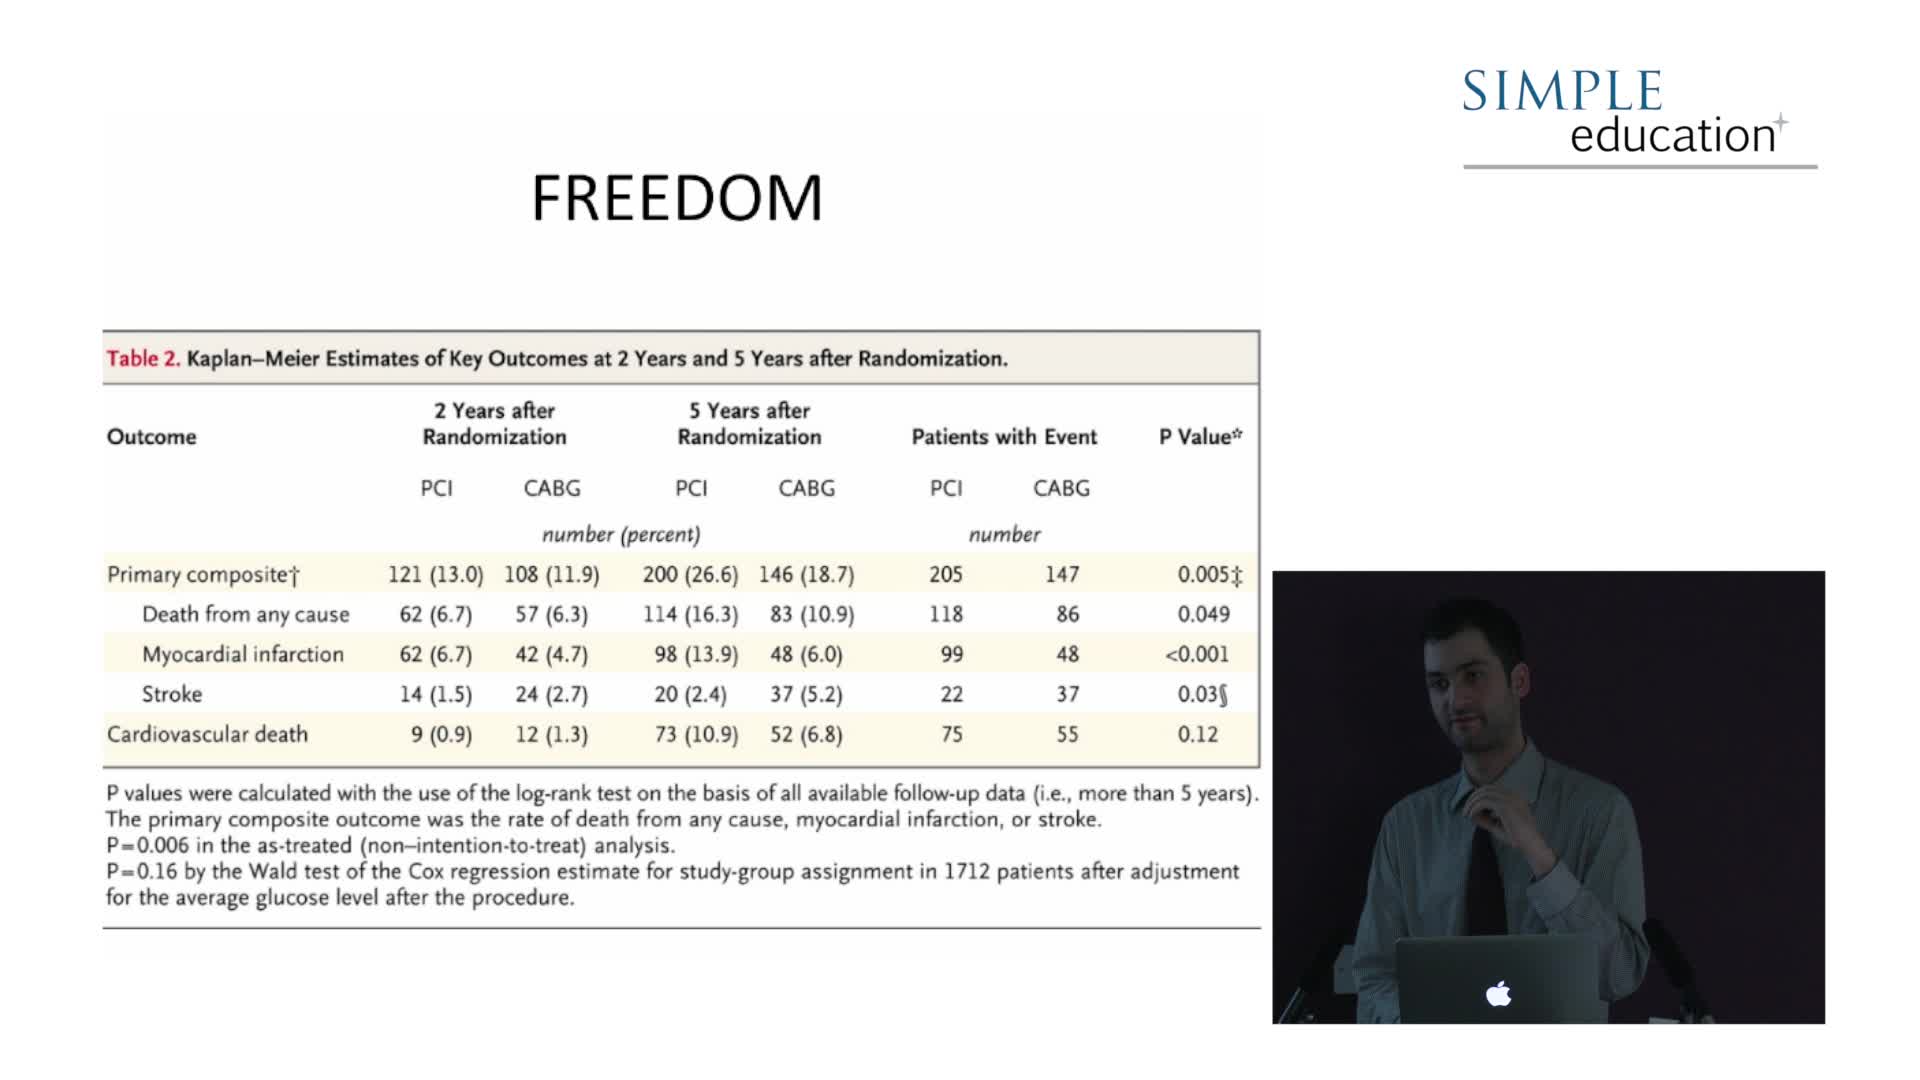

20 year overview of clinical trial data to support the use of coronary physiology in revascularisation decision-making